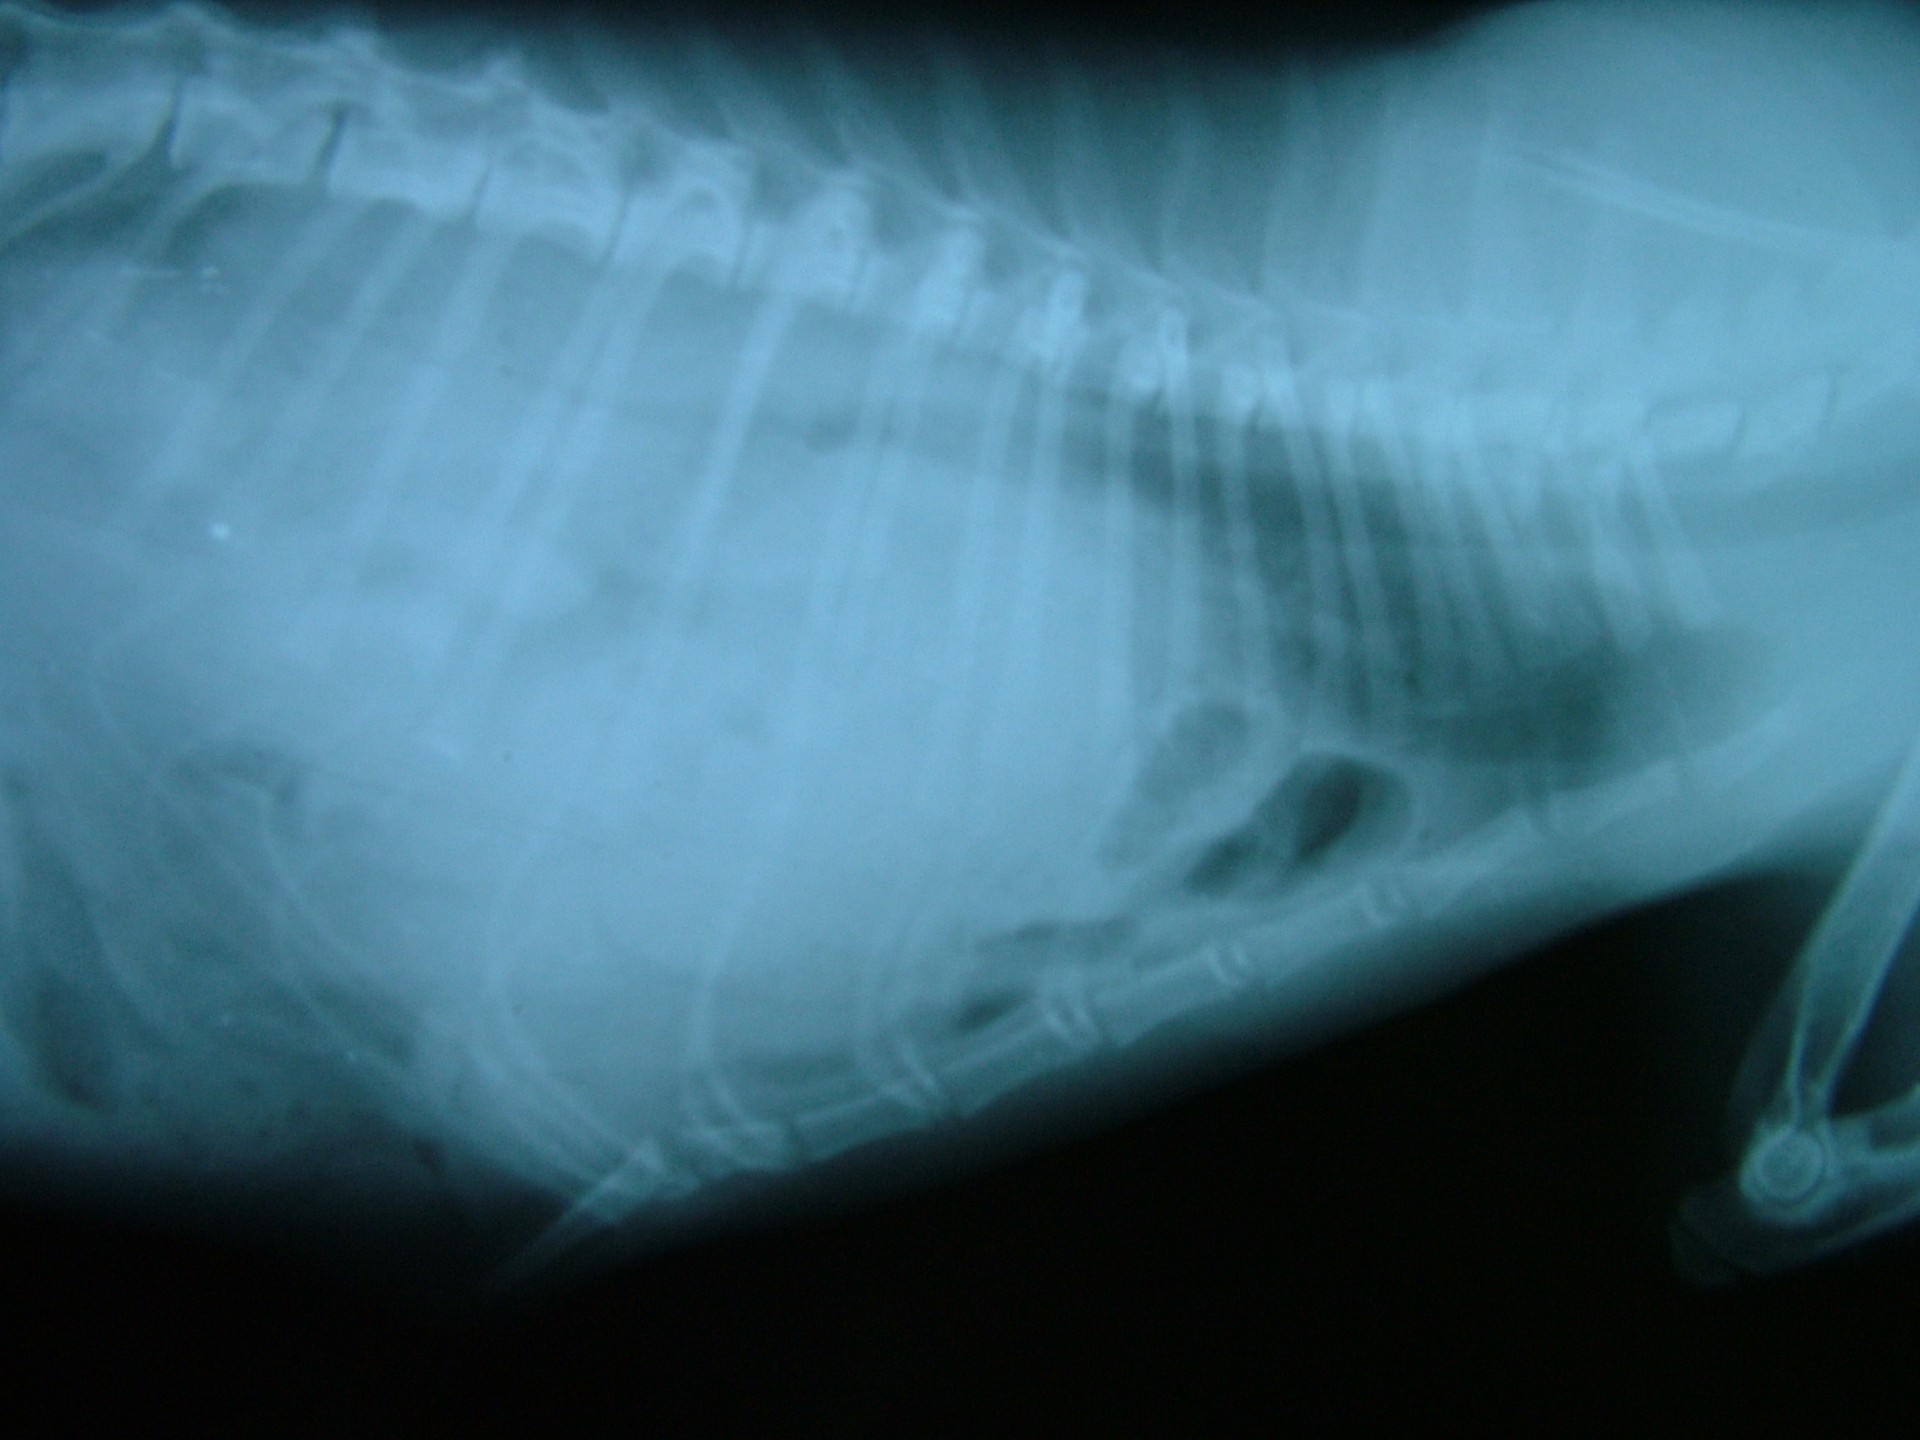

• A traumás eredetű rekeszsérv (hernia diaphragmatica traumatica) minden esetben valamilyen sérülést követően alakul ki. A rekesz folytonossága a sérülés következtében megszakad és az így kialakult sérvkapun keresztül a hasüregi szervek a mellüregbe előesnek. A betegség kórjóslata a trauma következtében kialakuló egyéb szervi sérülések miatt (máj-, léprepedés, tüdőzúzódás stb.) kifejezetten rossz. Az esetek döntő többségében az állatok súlyos általános állapotban kerülnek a rendelőbe, a diagnózis felállítását és a vérkeringés stabilizálását követően a traumás eredetű rekeszsérv azonnali műtéti ellátást igényel.

• Találkoztunk már olyan esettel is, amikor a tulajdonos a macskáját a traumát követően nem azonnal hozta az állatot ellátásra, ezért a traumás rekeszsérv diagnózisát néhány hónappal a sérülés után állítottuk fel (idült rekeszsérv, hernia diaphragmatica chronica). Ebben az esetben mérlegelni kell, hogy a hónapok alatt kialakult és stabilizálódott állapotot megbolygatjuk-e egy műtéttel vagy változatlanul hagyjuk. A műtét kockázatát ebben az esetben – a tulajdonossal való egyeztetést követően - nem vállaltuk.

Mindhárom rekeszsérv forma meglehetősen ritkán fordul elő. A diagnózis felállítása a kórelőzmény, a klinikai tünetek a mellkas röntgenvizsgálata, a hasüreg ultrahangos vizsgálata alapján lehetséges.A rekeszsérv műtéti ellátása során a legnagyobb kihívást az jelenti, hogy a hasüreg megnyitását követően a sérvkapun keresztül levegő kerül a mellüregbe, ezáltal az állat spontán légzése leáll, így a műtét teljes ideje alatt asszisztált lélegeztetésre van szüksége.A műtét során a mellkasba előesett szerveket reponáljuk, a rekesz folytonosság hiányát megszüntetjük és a mellkasban lévő szabad levegőt eltávolítjuk, ezzel biztosítva az állat spontán légzését. A műtétet követő napokban legfontosabb feladat a vérkeringés és a légzés folyamatos, kórházi körülmények közötti kontrolálása.Az idejében felismert és megfelelően ellátott veleszületett rekeszsérv jó eséllyel gyógyítható, a traumás eredetű sérv ellátásának eredményességét általában az egyéb szervek sérülése határozza meg.